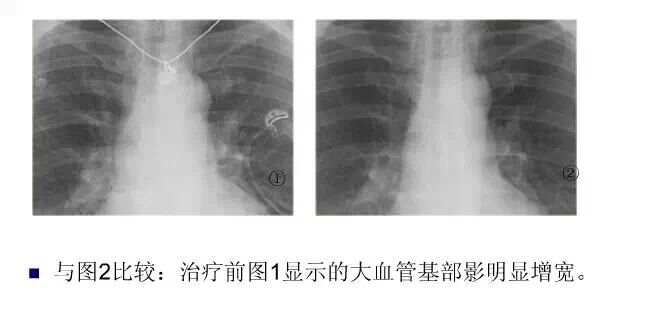

平片如何看心衰